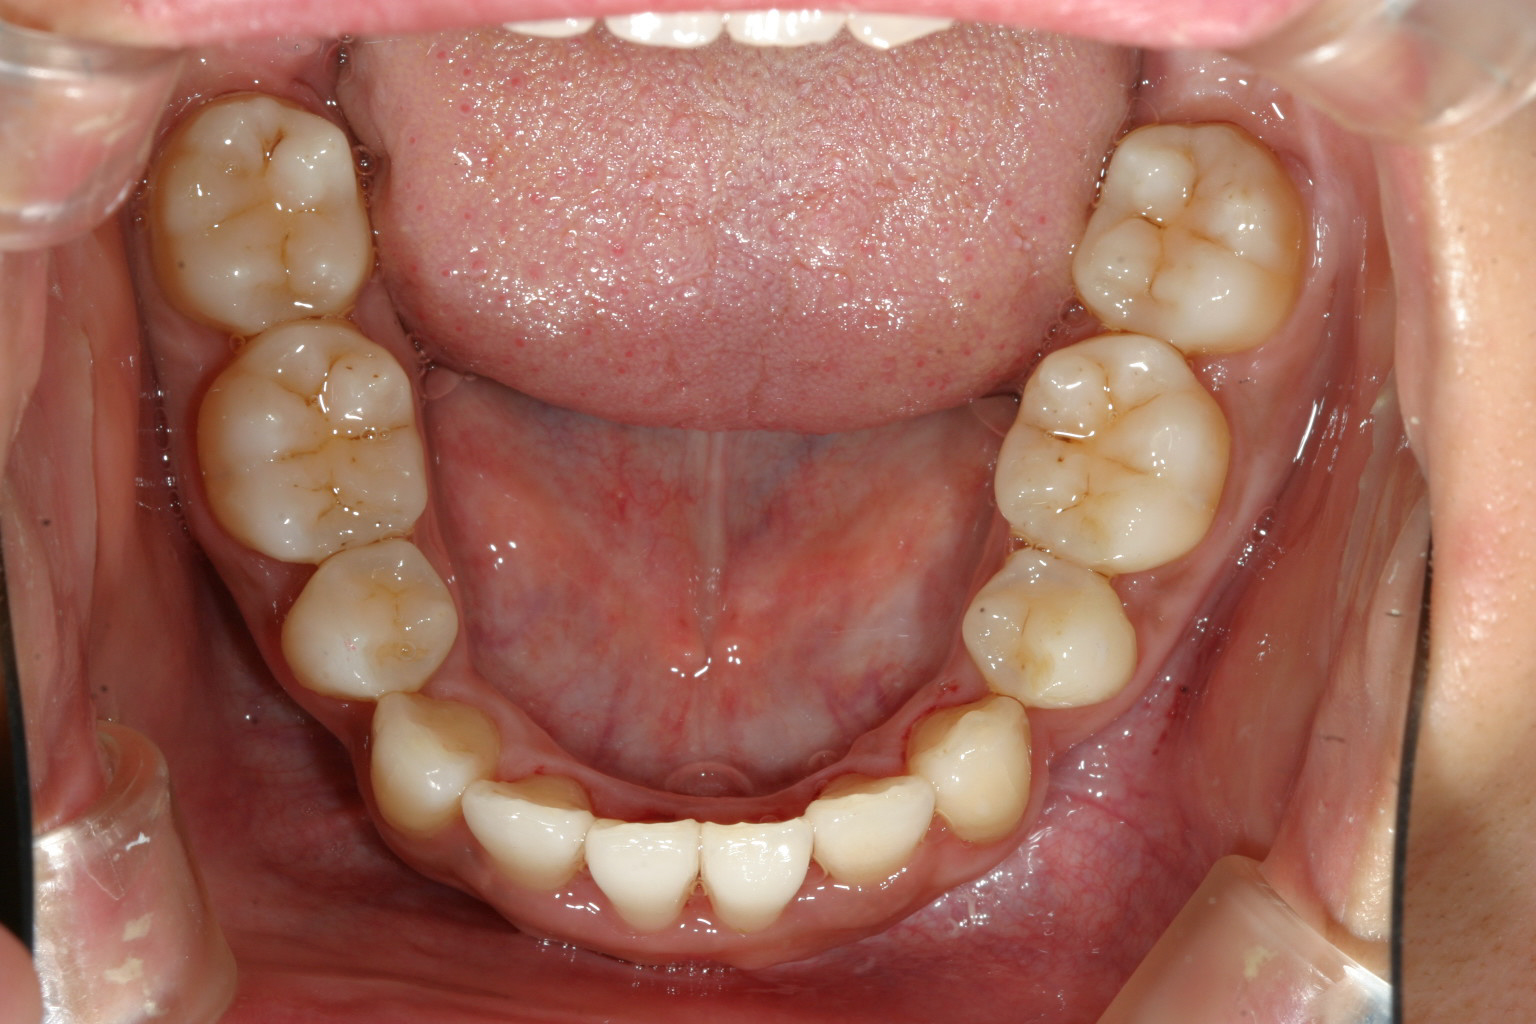

下顎も犬歯間が狭い為に前歯がバラバラになってます。

下顎も左右の糸切り歯抜歯して前歯のガタガタを取り除いています。